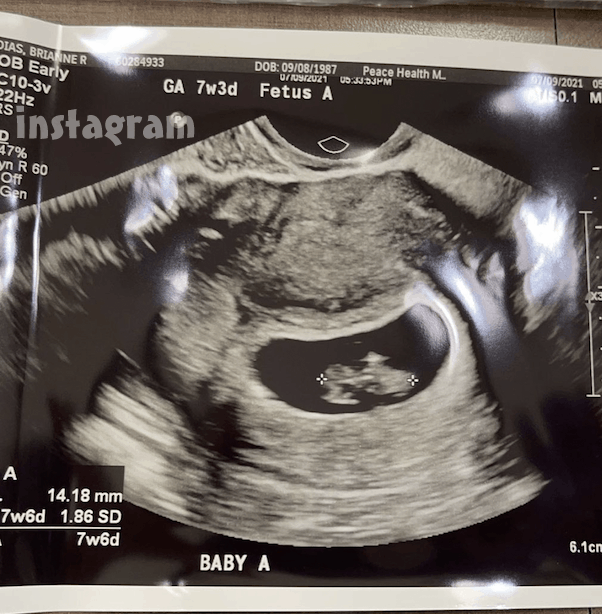

“Baby B didn’t have a heart beat,” she wrote. But that didn’t mean Brianne was no longer overjoyed by the prospect of becoming a mom: “Baby A is so perfect!” she went on. “Heart beat was 172!! I’m thinking girl!”

And here’s the sonogram of Brianne’s Baby A: